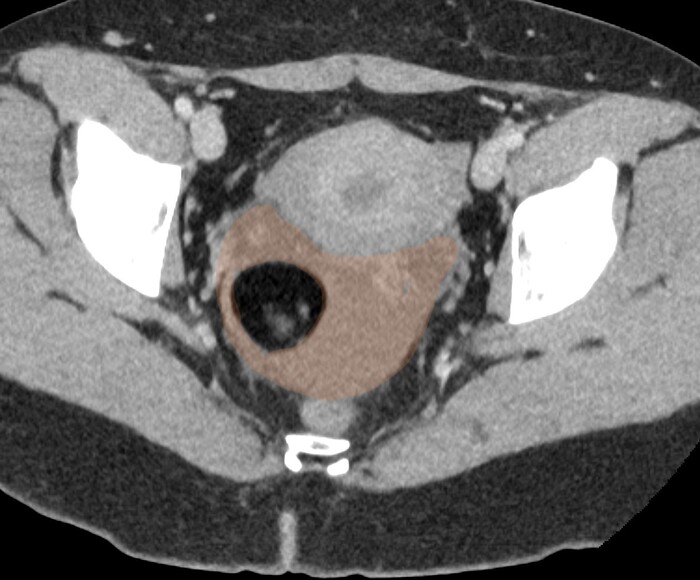

Однако в малом тазy, в области правого яичника было обнаружено округлое образование с чёткими контурами и размером 4 х 4 см, которое содержало преимущественно жир и некоторые плотные включения:

С определением типа образования правого яичника проблем особых не было: так выглядит классическая зрелая тератома на КТ.

Проблема была больше в выпоте с кровью в малом тазу, т.к. это не нормально (у женщин детородного возраста допускается некоторое количество свободной жидкости в малом тазу, но в совсем небольших и без значительных примесей крови), а значит тут, скорее всего, имеется острая патология, и скорее всего правого яичника в виде перекрута оного вокруг своей оси на фоне тератомы. При повторной оценке корональных срез было локализовано место перекрута (симптом "водоворота" сверху от правого яичника):